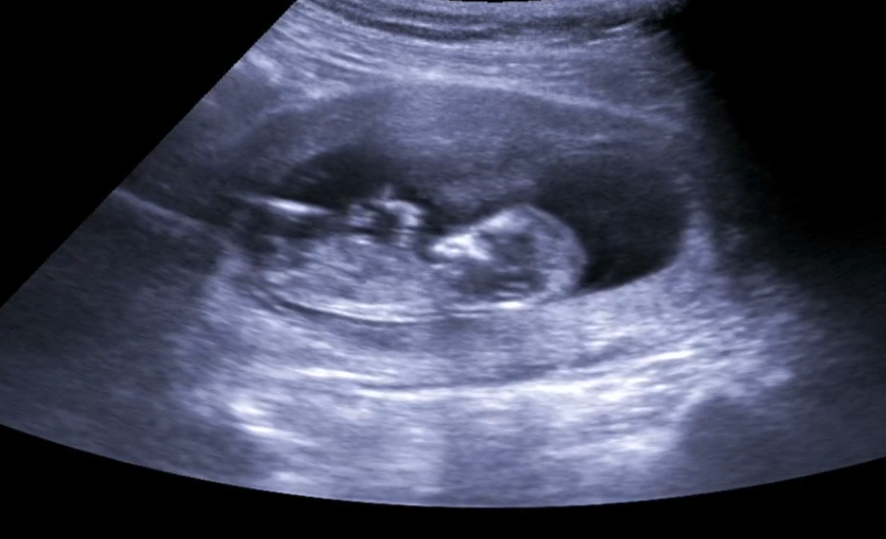

12주 2일 각도법 궁금해요!

장꾸맘카페는 여자만 가입이 가능해서 여기다 질문올려봅니당..! 이 모습으로도 각도법을 알 수 있다면 과연 아들딸 중 어디에 더 가까우려나요..?ㅎㅎ

의사쌤포함 아들이 압도적이군요ㅎㅎ